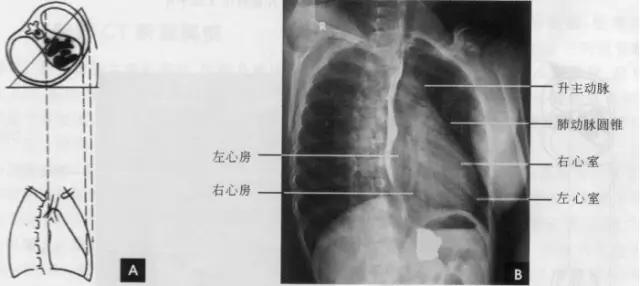

(三)左前斜位 从后前位向右旋转约60。得到左前斜位(又称第二斜位).此时室间隔与中心x线接*平近**行。因此.两个心室大致是对称的分为两半,前方一半为右心室.后方一半为左心室。心前缘上段为右心房.下段为右心室,右心房段主要由右心耳构成,房室分界不清。右心房影以上为升主动脉,两者相交成钝角:心后缘可分为上下两段,上段由左心房,下段则由左心室构成。左心室段的弧度较左心房大,两个不同弧度的交接点,可作为两者的分界。通过主动脉窗可兄气管分叉,主支气管和肺动脉,左主支气管下方为左心房影。左前斜位可了解各房室和主动脉情况(如下图)。